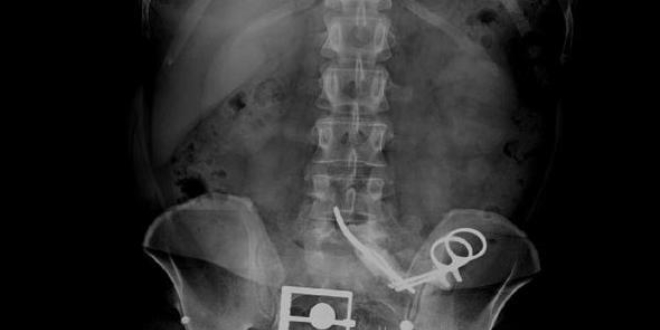

Adapazarı'nda F.D, 1995 yılı Mayıs ayında 19 yaşındayken rahatsızlığı nedeniyle Sakarya Devlet Hastanesi'ne gitti. Yapılan tetkiklerin ardından ameliyat edilen F.D.'nin dalağı alındı. Evlenip, bir çocuk sahibi olan F.D., bu tarihten sonra birçok kez hastaneye gitti, ancak karşılaştığı sağlık sorunlarında doktorlar MR veya röntgene gerek duymadı. Aradan geçen 23 yıl sonra, 1 Nisan'da bel ağrısı şikayetiyle Sakarya Üniversitesi Eğitim ve Araştırma Hastanesi'ne giden F.D.'yi muayene eden doktor, durumdan şüphe edince MR istedi. Doktor ayağında platin olduğunu ve cihaza yaklaşamayacağını söyleyen F.D.'yi bu kez röntgen çekilmesi için yönlendirdi. Röntgene bakan doktor, karın bölgesinde 13 santim uzunluğunda ameliyat makasının olduğunu tespit etti. Makasın, F.D.'nin 23 yıl önce geçirdiği dalak ameliyatında unutulduğu ortaya çıktı. F.D.'nin karnındaki makas, başarılı bir operasyonla alındı. F.D.'nin durum fark edilmeden önce MR için cihaza girmiş olması durumunda makasın iç organlarını parçalayabileceği belirtildi.